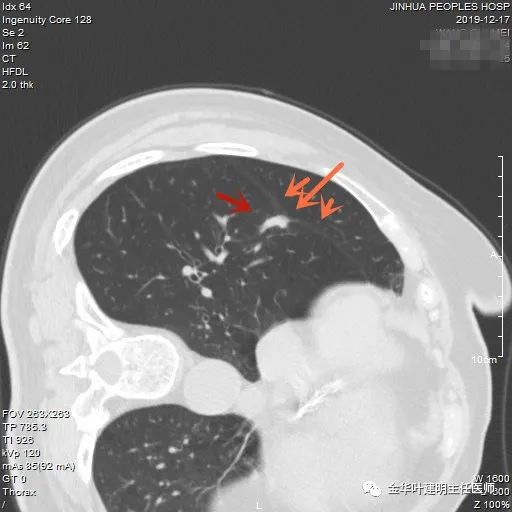

上图也是浸润性腺癌。但病灶长条状,就像慢性炎,叶间胸膜牵拉较明显,也符合瘢痕收缩,又不是圆形或类圆形。